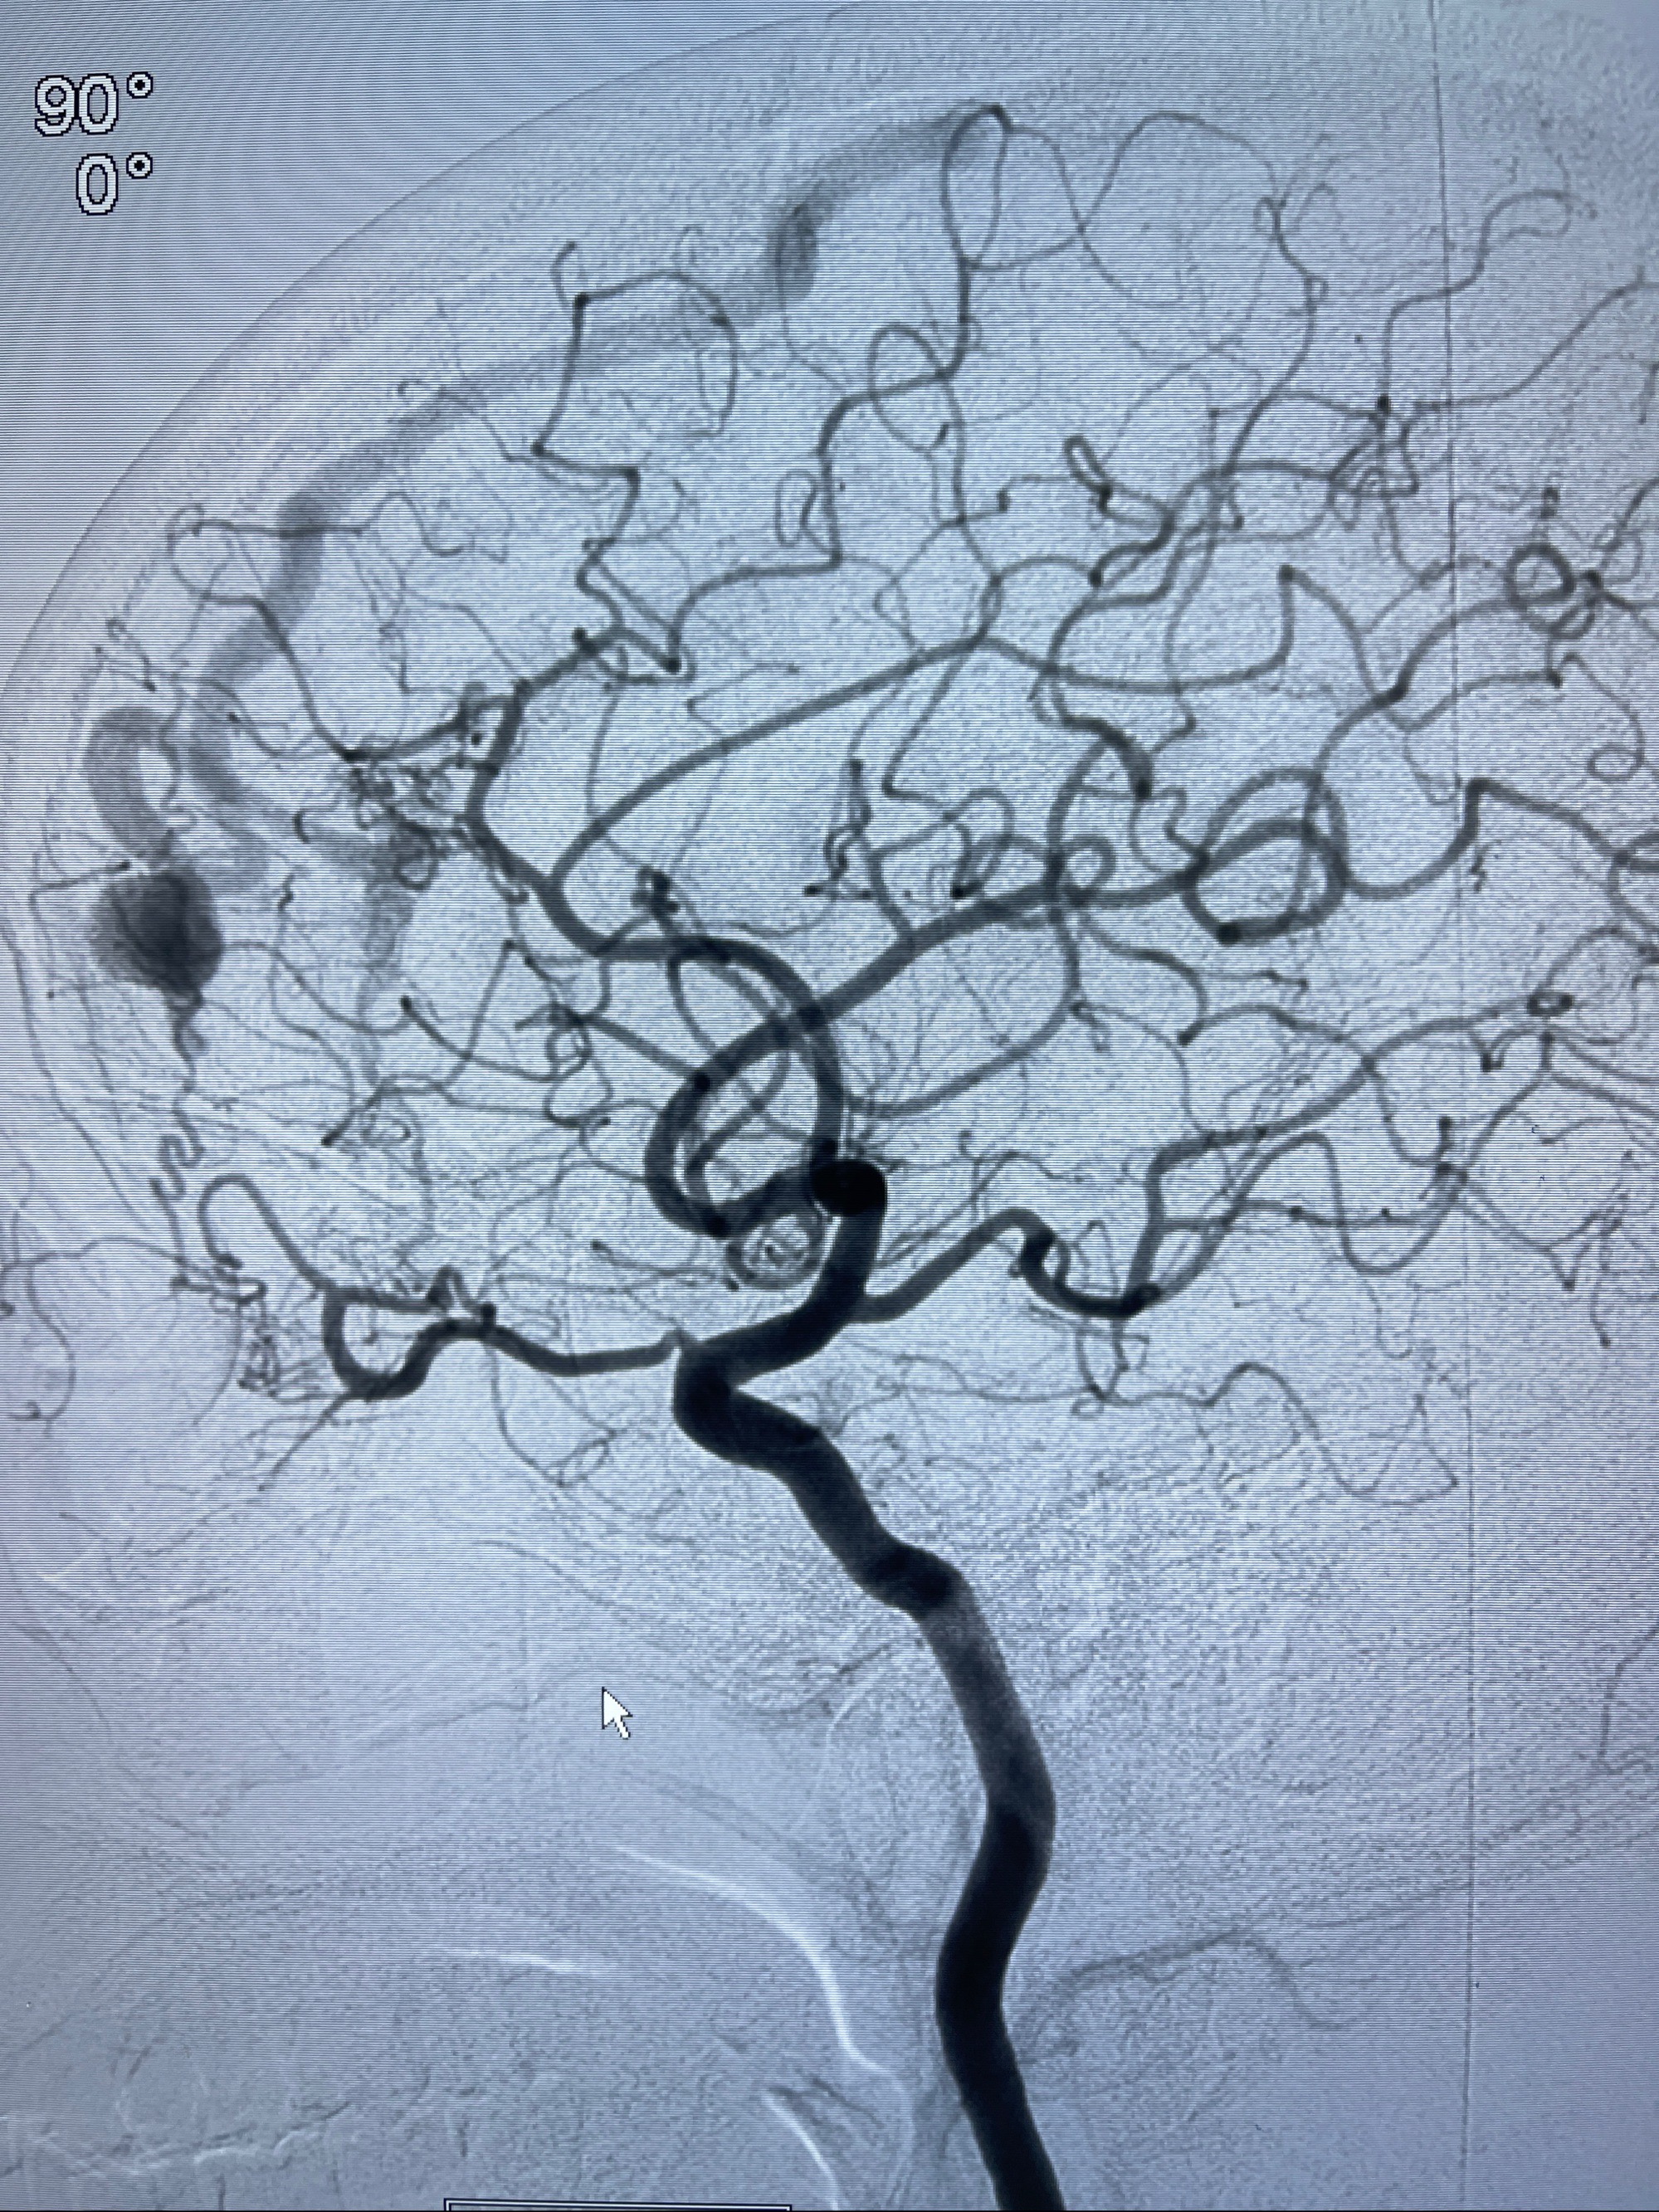

2023年8月21日]景德镇市第一人民医院脑血管造影检查,提示:主动脉弓、双侧颈总动脉、锁骨下动脉造影未见异常,左侧大脑前动脉静脉瘘。

2023-09-13全脑血管造影:前颅底硬脑膜动静脉瘘,供血动脉为双侧胼周动脉、眼动脉脑膜支,静脉向上矢状窦方向引流